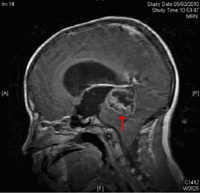

Varón de 13 años diagnosticado de SN, con mutación en el gen PTPN11, en tratamiento con hormona de crecimiento (GH) desde hace 3 meses, remitido a nuestro servicio por cefalea pancraneal, evidenciándose en la exploración ocular papiledema; el estudio del campo visual (CV) muestra afectación “sin patrón” de predominio en hemicampos izquierdos (Figuras 1a y 1b). El servicio de Pediatría realiza un diagnóstico inicial de HIC benigna posiblemente relacionada con la administración de GH, por lo que es suspendida. A la semana acude al servicio de urgencias por un episodio de cefalea acompañada de vómitos en escopetazo y ataxia. Se “agiliza” la realización estudios de neuroimagen (TAC y RMN) solicitados previamente, observándose en los mismos la presencia de hidrocefalia y de una tumoración en fosa posterior (Figura 2). El servicio de Neurocirugía realiza una derivación ventrículo-peritoneal y extirpación del tumor. Como secuela postquirúrgica el paciente presenta paresia del III par bilateral y paresia del VI par izquierdo. El estudio histopatológico del material extraído confirma el diagnóstico de ependimoma grado II OMS (Figura 3).

Figura 2. RMN T1 sagital inicial tras administración de contraste con Gadolinio: se observa tumoración que capta contraste en la periferia pero no en el centro debido a la necrosis tumoral, se observa la presencia de gran dilatación ventricular, como se observa a nivel de la silla turca

En la RMN de control se observan dos áreas de captación patológica de Gadolinio, una en la vertiente superior y lateral izquierda de 1 cm y otra en la vertiente anterior y lateral derecha del cuarto ventrículo, por lo que el paciente es remitido al hospital de referencia (Hospital Vall d´Hebron, Barcelona), para realizarle tratamiento radioterápico focal con fraccionamiento diario de 1.8 Gy y dosis total de 56 Gy. En la actualidad se aprecia una afectación bilateral incompleta del III par con leve ptosis, VI par izquierdo, sin diplopía en posición primaria de la mirada, palidez papilar (Figura 4), test de visión binocular negativos, mejoría franca del CV, y estudios de neuroimagen sin evidencia de hidrocefalia ni del tumor.